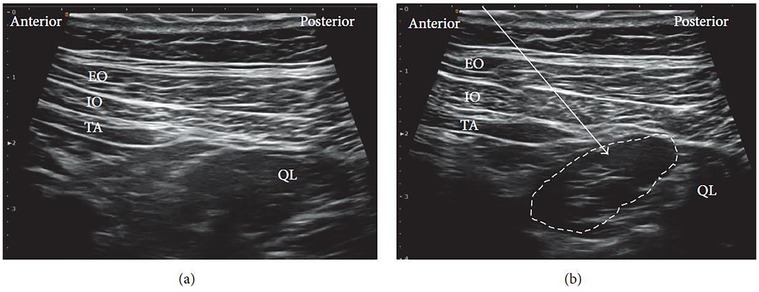

The patient is usually positioned supine, as in the lateral QLB. In some cases, placing a pillow beneath the back can improve the working field and facilitate probe maneuverability. A low-frequency curvilinear ultrasound probe is most commonly employed. Under ultrasound guidance, the posterior margin of the QL muscle is identified, and the needle is advanced until the tip reaches this fascial plane (Figure 4a). Local anesthetic is then injected within the LIFT, situated posterior to the QL (Figure 4b).

Figure 4

Ultrasound images showing the quadratus lumborum (QL) muscle marked by a dashed outline. The anterior to posterior layers are labeled as external oblique (EO), internal oblique (IO), and transversus abdominis (TA). Panel (a) and panel (b) display slight variations in the depiction of muscle boundaries and labeling.

Figure 4. Ultrasound images of posterior QLB: (a) before injection and (b) after injection. EO, external oblique; IO, internal oblique; TA, transversus abdominis; QL, quadratus lumborum. White arrow: needle trajectory; white dotted line: spread of local anesthetic [Reproduced from Ueshima et al. (28). © John Wiley & Sons, Inc. Distributed under the Creative Commons Attribution License, CC BY 4.0].